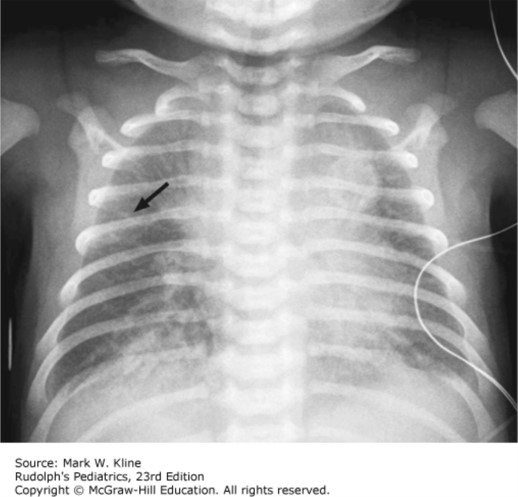

The infant girl is vigorous after delivery, with Apgar scores of 8 and 8. She is brought to her mother’s chest. Fifteen minutes later the NICU team is called because the infant is experiencing worsening respiratory distress with tachypnea, retractions, and mild grunting respirations. She is placed on nasal continuous positive airway pressure (CPAP) and admitted to the NICU. The infant shows clinical improvement on CPAP, requiring approximately 25% FiO2. Her chest radiograph shows 10-rib expansion with fluid in the fissure and no other focal infiltrates. You are asked to update her family.

The correct answer is “C.” Transient tachypnea of the newborn is most common in late preterm and term infants who are delivered by cesarean section or precipitous delivery. Chest films demonstrate adequate lung expansion with retained fetal lung fluid. This condition generally improves quickly over hours and affected infants very rarely need intubation and mechanical ventilation.